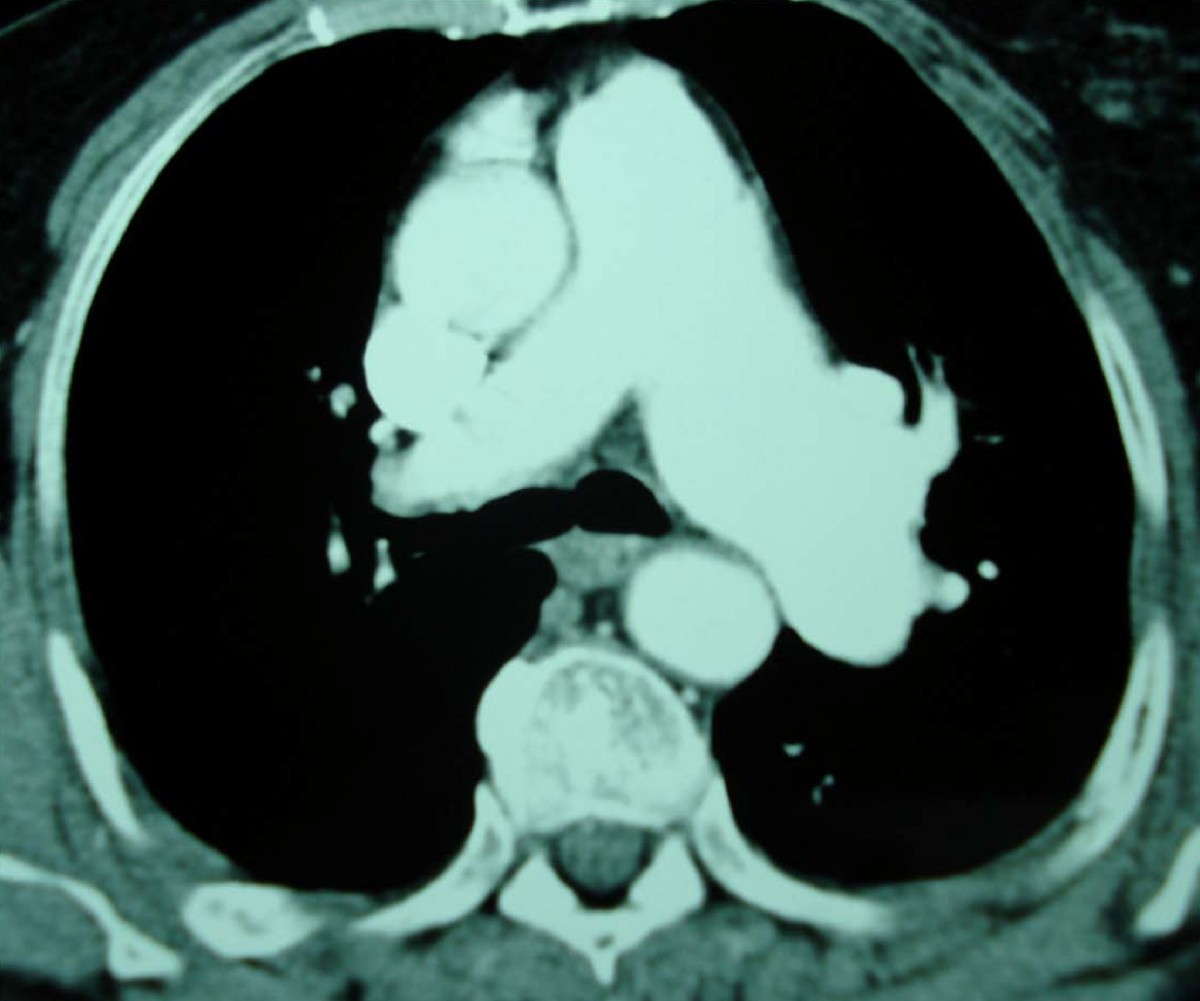

From rc.rcjournal.com

A Lesson from a Rare Cause of Pulmonary Embolism Respiratory Care Can Low Blood Pressure Cause Pulmonary Embolism A pulmonary embolism (pe) occurs when a blood clot obstructs the pulmonary artery or its branches. For example, shortness of breath on exertion or intermittent chest pains. Pulmonary embolism can be classified depending on degree of pulmonary vasculature obstructed by burden of blood clots. In 10 percent to 15 percent of pulmonary embolism patients, the condition causes low blood pressure. Can Low Blood Pressure Cause Pulmonary Embolism.